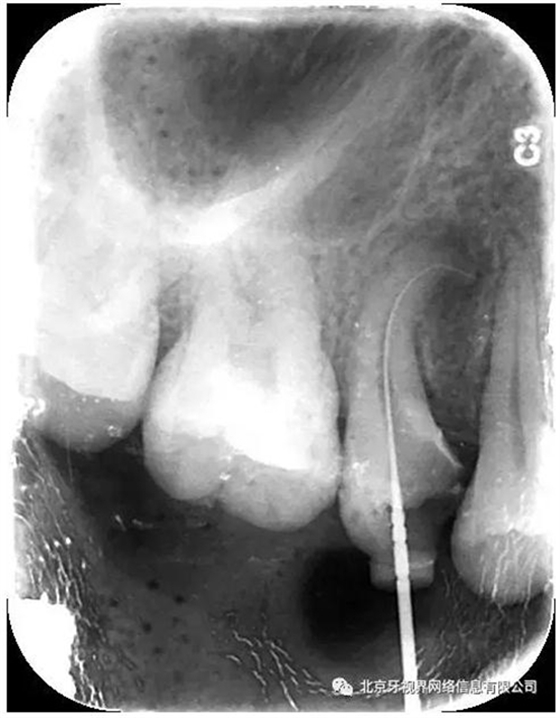

15備洞,揭頂,10#擴大器預彎后疏通至全長,次氯酸鈉加超聲蕩洗,氫氧化鈣糊劑封藥,玻璃離子暫封,隨診。

4.此例病例中,術(shù)前分析后,采取先解放其中上段后,10#擴大器預彎緩慢前行,抵達根尖區(qū)。